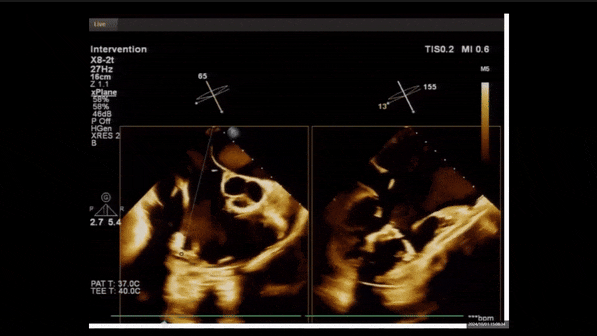

夾持件位置確認(rèn)

室間隔位置確認(rèn)

術(shù)中經(jīng)食道超聲輔助下可見LuX-Valve Plus夾持件抓捕瓣葉狀態(tài)良好,夾持件在位,室間隔錨定位置良好,假體瓣膜整體錨定狀態(tài)穩(wěn)固。